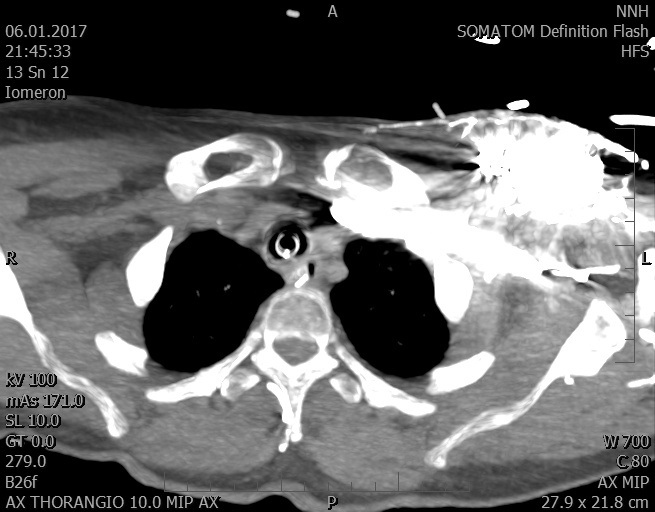

Video 1 - Akutní koronarografie prokázala normální nález na věnčitých tepnách s výjimkou suspekce na lehký spasmus na pravé koronární tepně.Echokardiograficky byla zjištěna těžká dysfunkce dilatované levé komory s nezvětšenou pravou komorou (video 2).

Video 2 - Echokardiograficky byla zjištěna těžká dysfunkce dilatační levé komory s nezvětšenou pravou komorou.Pro nejasnou příčinu zástavy jsme provedli i vyšetření výpočetní tomografií (CT), které vyloučilo plicní embolizaci (série 1 - soubory na konci článku). V den přijetí při přetrvávající oběhové nestabilitě byla nemocná opakovaně defibrilována pro fibrilaci komor se stabilizací rytmu po podání amiodaronu a mesocainu. Dle hemodynamických měření se jednalo o těžký kombinovaný šok. Vstupní laboratorní vyšetření bylo bez větších pozoruhodností. Posléze jsme doplnili anamnézu od příbuzných a zjistili, že pacientka užila do dvou hodin před srdeční zástavou první tabletu amoxicilinu na lehký respirační infekt. Při nevýtěžnosti vstupních vyšetření a nových anamnestických informacích jsme doplnili 14 hodin po kolapsu vyšetření koncentrace tryptázy v séru, která byla extrémně zvýšena (tabulka 2), což nás vedlo k podezření na anafylaxi.